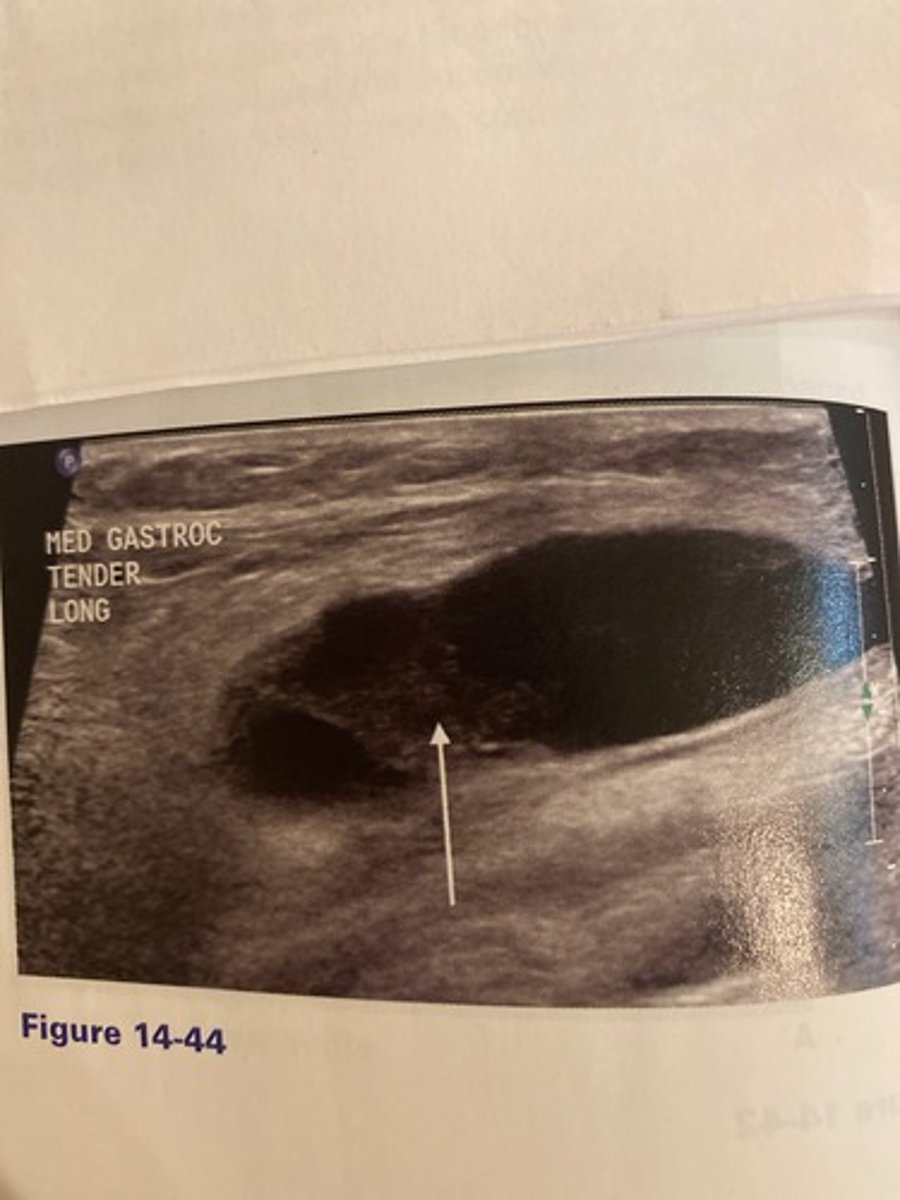

The arrow in Figure 14-44 indicates hemorrhage within a mass noted behind the knee. Which of the following would be the least helpful task the the sonographer should perform in this case?

a. Apply color Doppler.

b. Perform the Thompson test.

c. Inquire if the patient has a history of rheumatoid arthritis.

d. Analyze the cyst for evidence of channel leading to the joint.